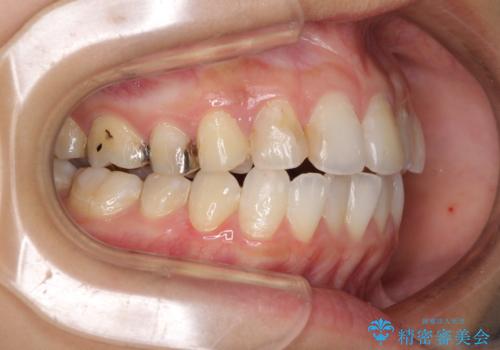

後戻りを治したい 骨格的なズレの大きい方のインビザライン矯正

- 中学生の時に矯正治療をしたものの、後戻りを気にして来院された患者様です。

骨格的に下顎が右側に変位しているため、左右の咬み合わせを理想的なものに改善することはできませんが、インビザラインにて歯列を整えることとしました。

骨格的なズレによる左右差は改善できませんでしたが、上下の正中を極力合わせるようにすることができました。